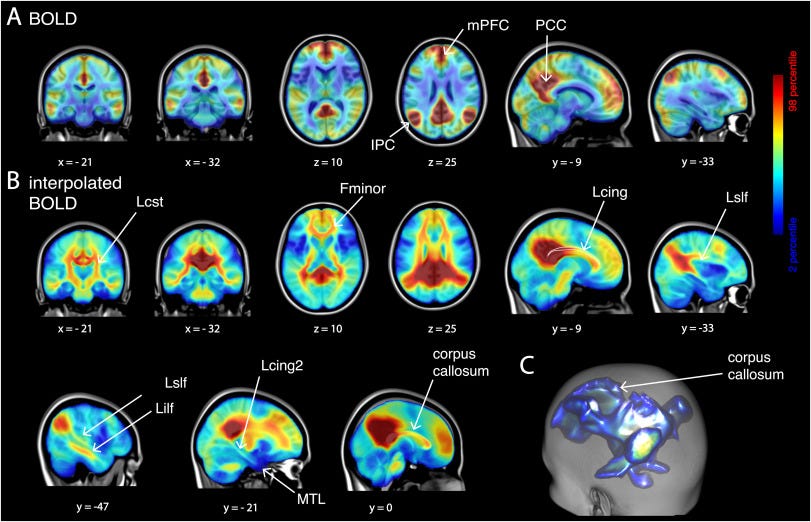

ولفهم هذه الظاهرة بشكل أدق، أجرى فريق بحثي بقيادة عالمة وظائف الأعصاب أناليزا باسكيلا دراسة استخدم فيها تقنيات تصوير دماغي عالية الدقة، إلى جانب أدوات متقدمة في التعلّم الآلي. وقد سمحت هذه الأدوات للباحثين بتحليل الأنماط المعقّدة لنشاط الدماغ لدى المتأملين، ومراقبة كيفية انتقاله بين الفوضى والنظام، وصولًا إلى حالة التوازن التي تُعدّ ضرورية للصحة الذهنية والأداء المعرفي السليم.

في المرحلة الأولى من الدراسة، اعتمد الباحثون على تقنية تخطيط الدماغ المغناطيسي (MEG) لقياس نشاط الدماغ أثناء ممارسة التأمل، ومقارنته بحالة الراحة الذهنية غير التأملية. وتقوم هذه التقنية على رصد المجالات المغناطيسية الدقيقة التي تنتج عن الإشارات الكهربائية الصادرة من الخلايا العصبية، ما يسمح بتتبّع نشاط الدماغ بدقة زمنية عالية دون تدخل مباشر.